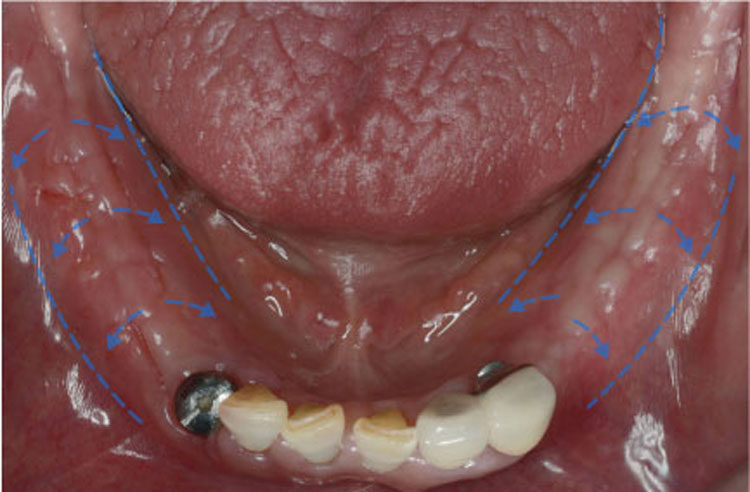

1_뼈이식_후.jpg

치료후 : 2019-12-31

세종치과는 많은 환자와 다양한 케이스를 바탕으로

항상 편안한 임플란트 수술을 제공하고자 노력하고,

오래동안 튼튼히 쓸 수 있는 임플란트 수술을 가장 큰 목표로 삼고 있습니다